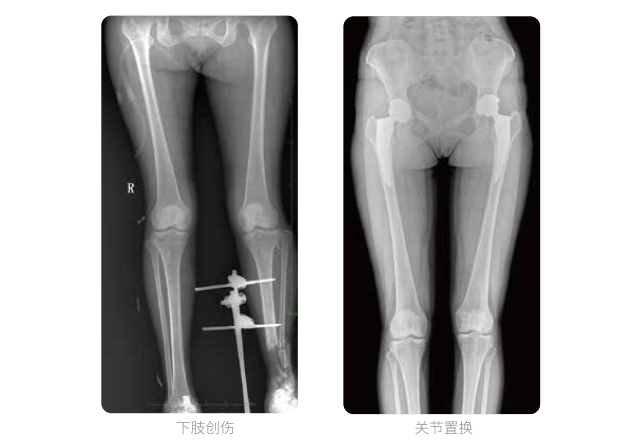

一次曝光 讓較長髓內(nèi)釘細(xì)節(jié)畢現(xiàn)

雙下肢臨床影像

髓內(nèi)釘手術(shù)是骨科、手足外科中常見的微創(chuàng)型手術(shù)方式,患者隨訪時需拍攝置入在股骨、肱骨處的較長髓內(nèi)釘。PLX8600視野拍攝,能夠出色解決醫(yī)生需多次攝影再拼接的痛點。一次成像雙下肢,即拍即得,高效率,無需拼接。工作站軟件自帶的測量功能方便醫(yī)生讀取雙下肢長度數(shù)據(jù),助力準(zhǔn)確診斷。

動態(tài)DR所具備的全脊柱、全下肢全景成像技術(shù)檢查,能夠更加清晰的顯示患者病情變化情況,對骨科疾病患者的全脊柱、全下肢病變情況圖像展示更加具有完整性,對患者在自然狀態(tài)下的應(yīng)力情況展示較為全面,有助于骨科疾病患者臨床診斷效果的提升,對患者臨床治療方案的科學(xué)制定有著積極的作用。